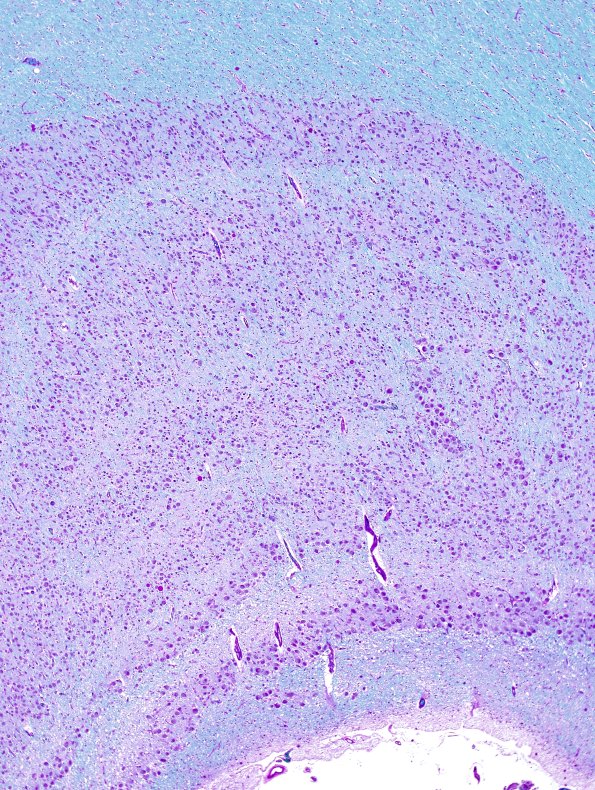

Washington University Experience | NORMAL | Hippocampus & LGN | 1B2 Hippocampus, normal (Case 1) LFB-PAS 4X